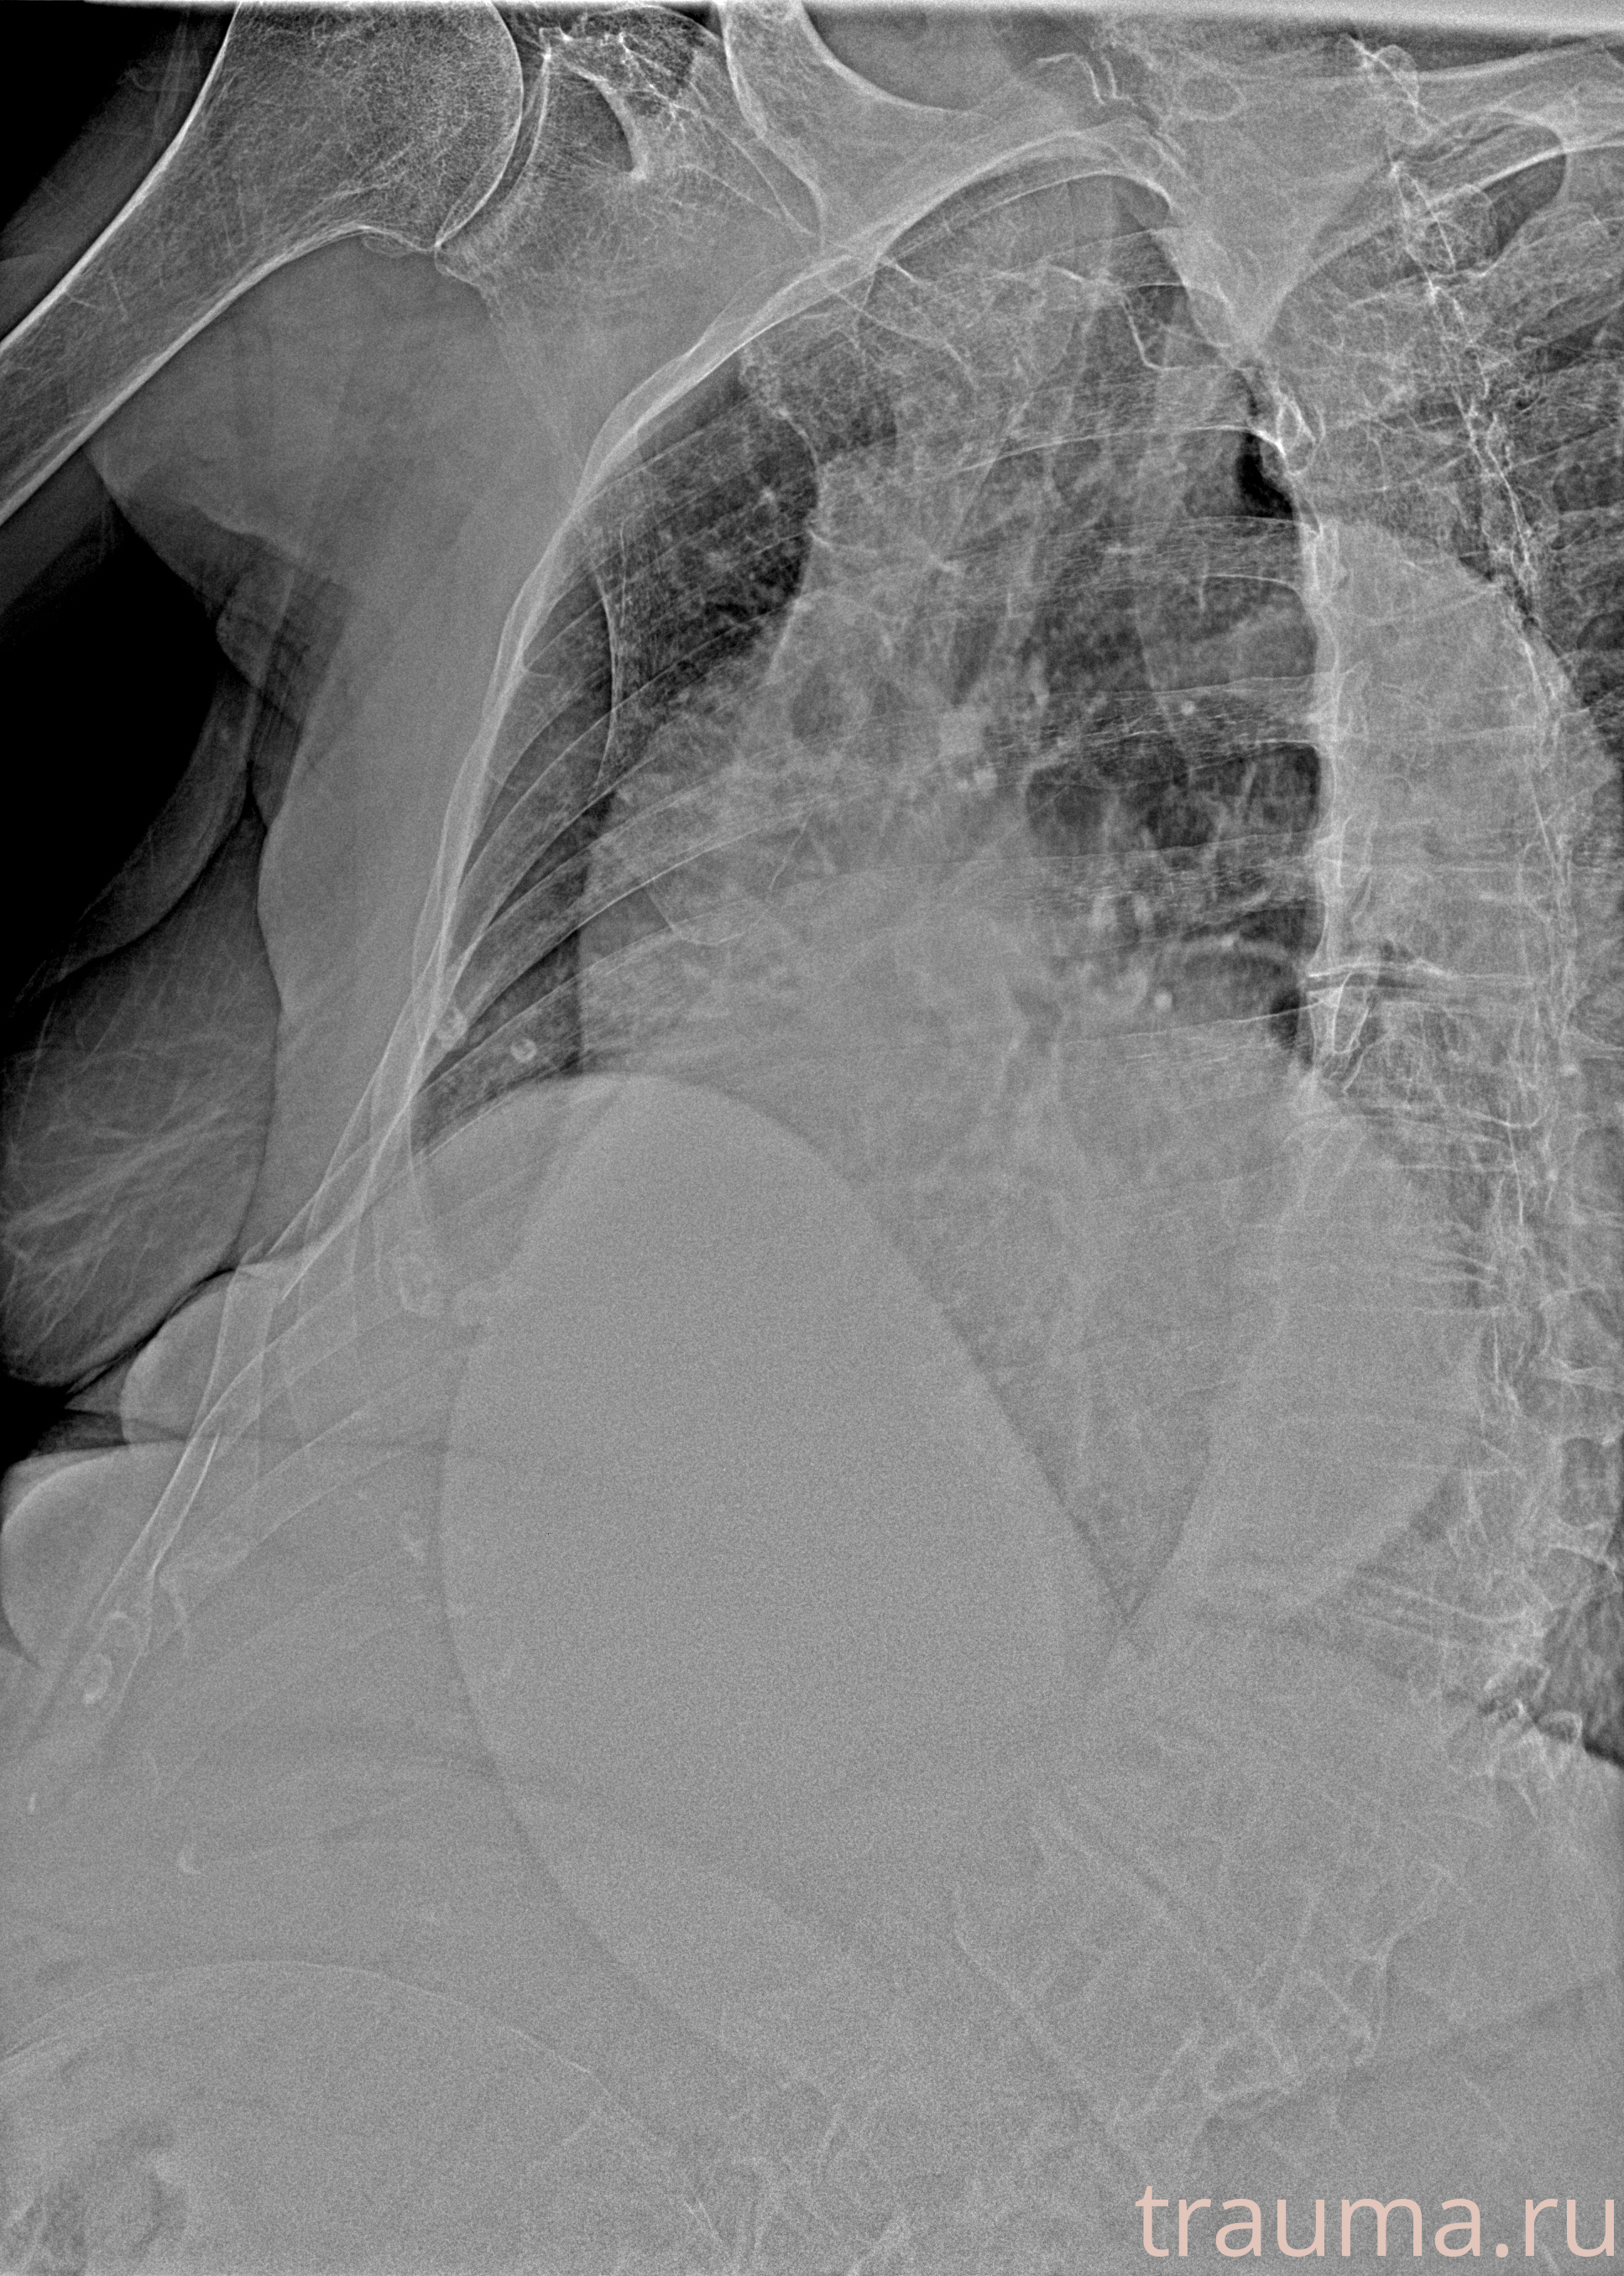

Рентген на дому: по вашему адресу приезжает врач-рентгенолог, травматолог-ортопед с мобильным рентгеновским аппаратом, проводит диагностику травмы или заболевания, делает необходимые рентгенограммы, дает рекомендации по дальнейшему лечению. Получить качественные снимки в домашних условиях возможно благодаря уникальной методике, разработанной МосРентген Центром для института  Склифосовского